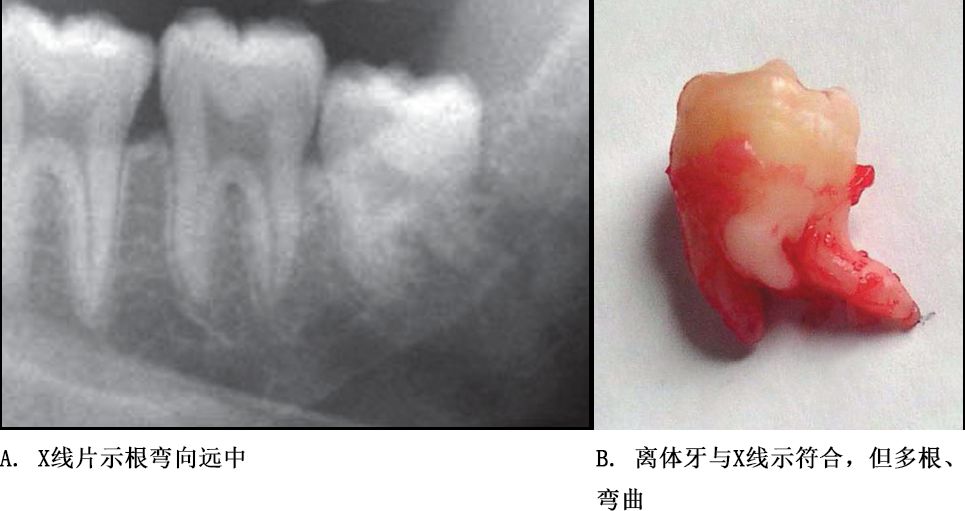

牙根阻力以多根牙、根分歧过大、特长根、U形根、牙颈部倒凹大者阻力较大根尖区以近中弯曲、多向弯曲、根尖肥大者牙根阻力较大。

根部阻力较大者的智齿形态